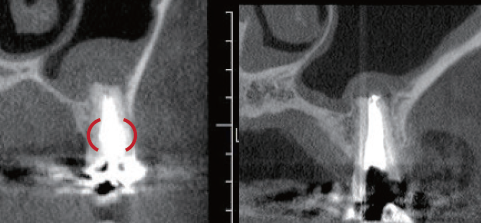

左上1番の根尖部にMTA製剤充填時のCBCT像

唇側皮質骨は大きく開窓し、根尖病変の大きさが鼻腔底付近まで広がっていることが確認できる

臨床症例3 その5

術後1年のCBCT像

根尖周囲に見られた根尖病変はほぼ消失し、唇側皮質骨の開窓も改善したことが認められる